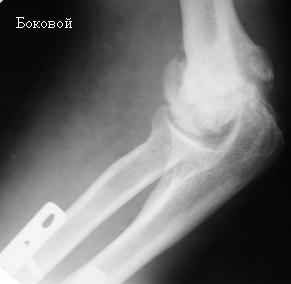

Стойкая комбинированная контрактура правого локтевого сустава

Увжаемые коллеги! На консультации больной со стойкой комбинированной контрактурой правого локтевого сустава.

В прошлом - спортсмен, сейчас охранник. Травма 2 августа 2008г., автодорожная. Оперирован в одной из больниц города. Остеосинтез, два месяца гипс. Объем движений с тех пор не изменился. Боли после физнагрузки (пытается тренироваться).